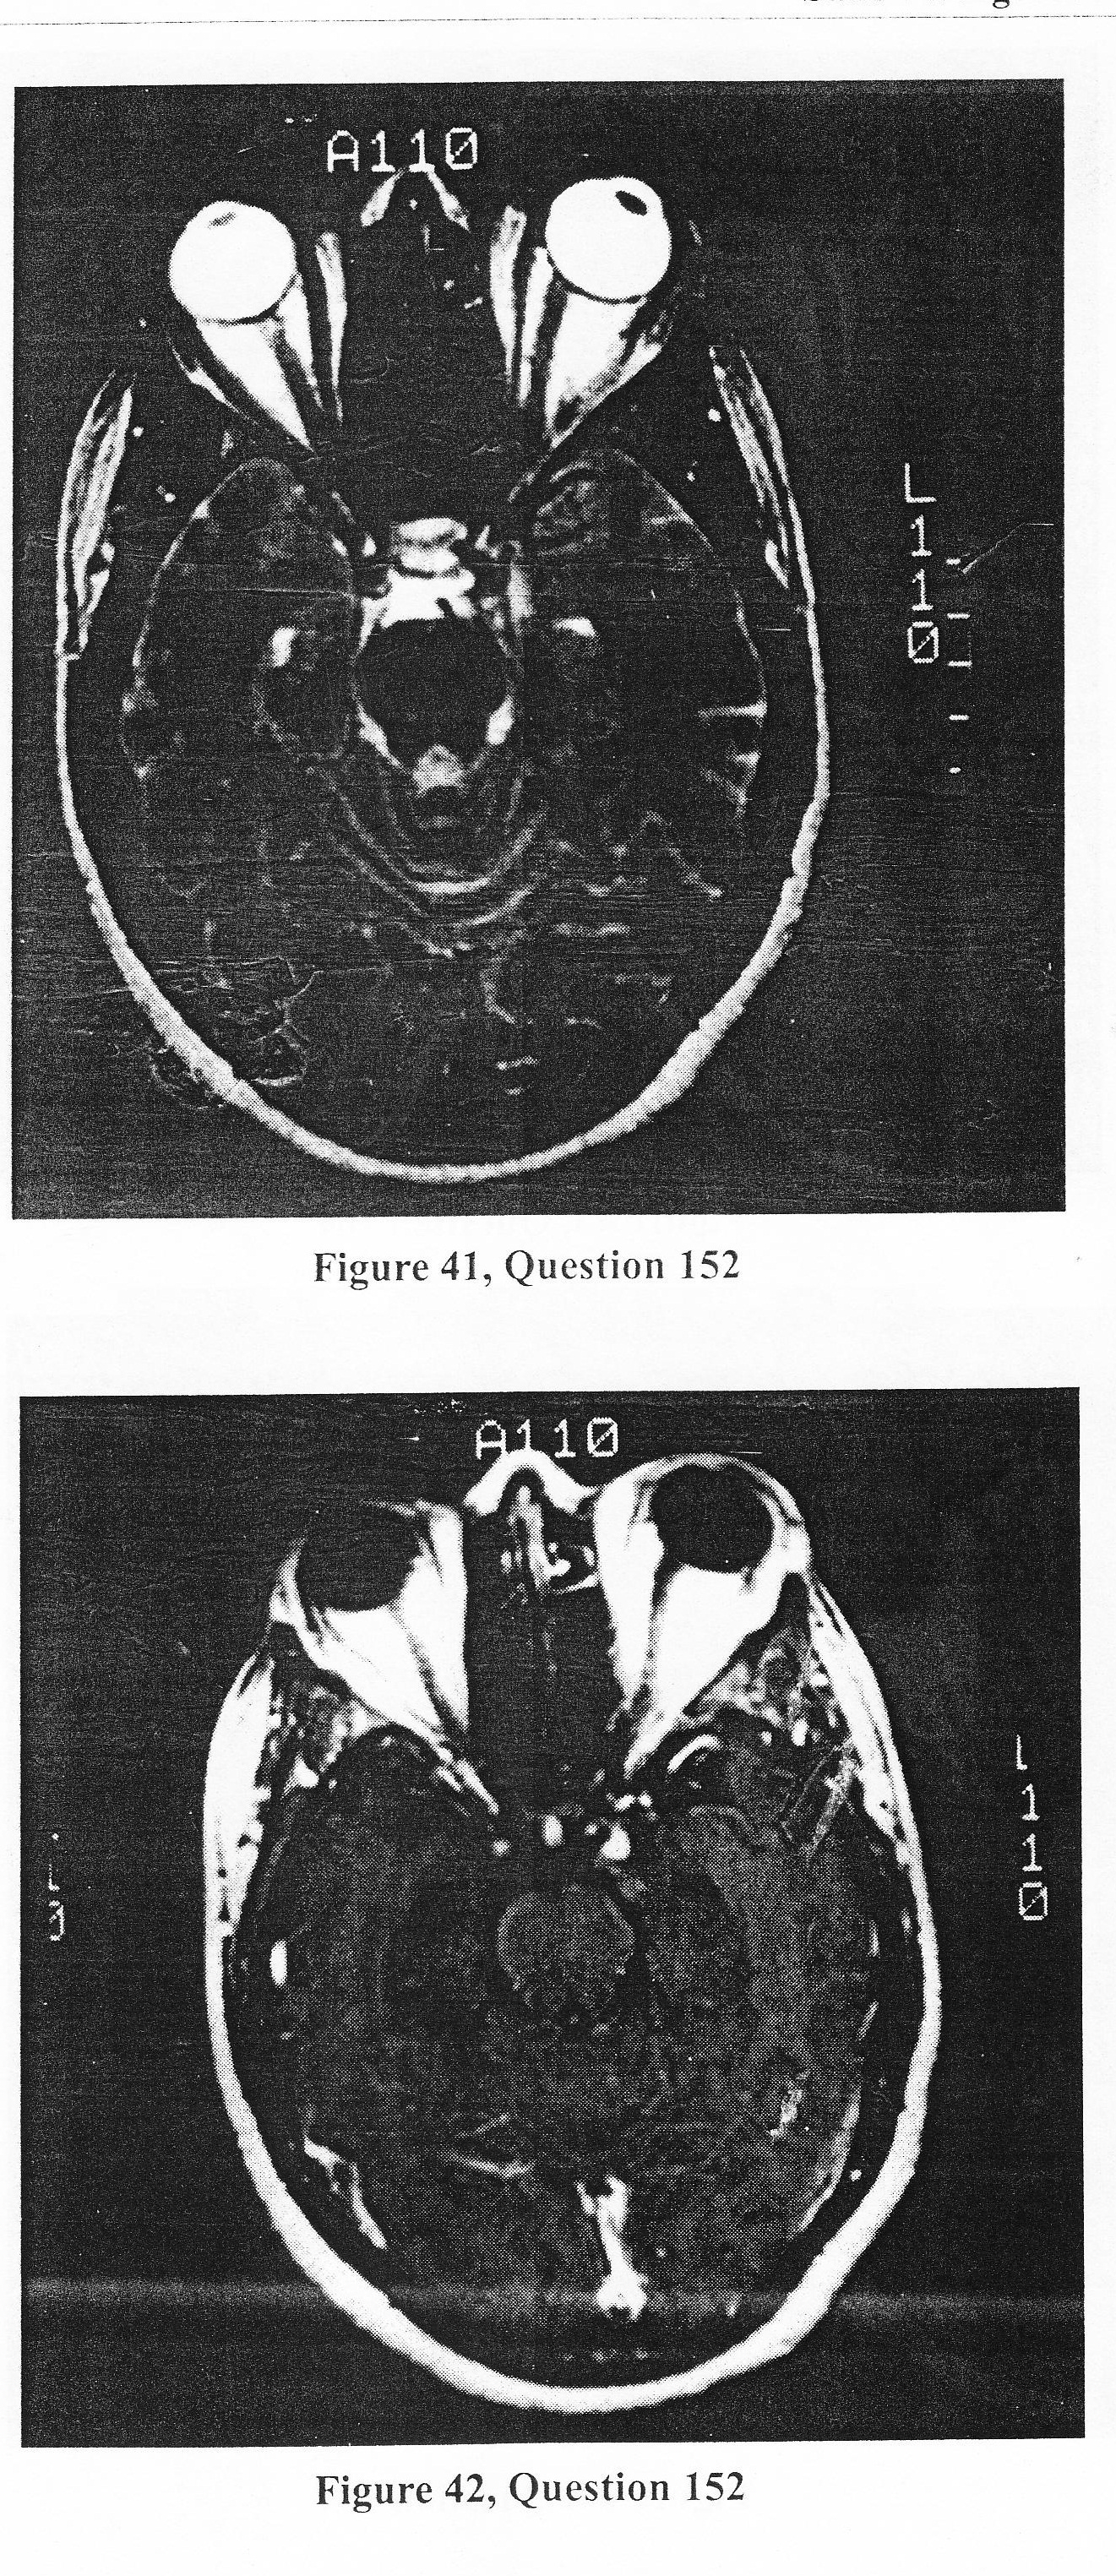

A 40-year-old black female presents to the emergency room complaining of sudden onset of left sided periorbital pain and headache with the inability to open her left eye. Two weeks previously, she was seen in the emergency room complaining of severe diffuse headache and sent home with the diagnosis of tension headaches. On exam, she had no nuchal rigidity or photophobia. She was alert and oriented. She could not elevate her left eyelid or look medially. Her pupil was dilated and reacted minimally to light.

C. The patient needs an angiogram to rule out a posterior communicating artery aneurysm.